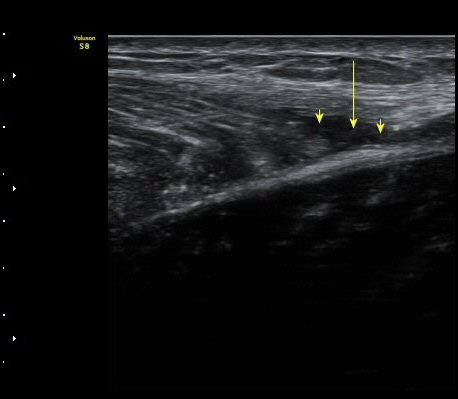

¼ö»ó ÈÄ 2ÁÖ Â°

³»Ãø ºñ·Ï±Ù Á¾´Ü¸é°Ë»ç¿Í Ⱦ´Ü¸é°Ë»ç¿¡¼­ ºñº¹±Ù°ú °¡Àڹ̱ٻçÀÌ¿¡ Ç÷¾×ÀÌ °í¿© ÀÖÀ½

(±×¸² 5, 6, 7).